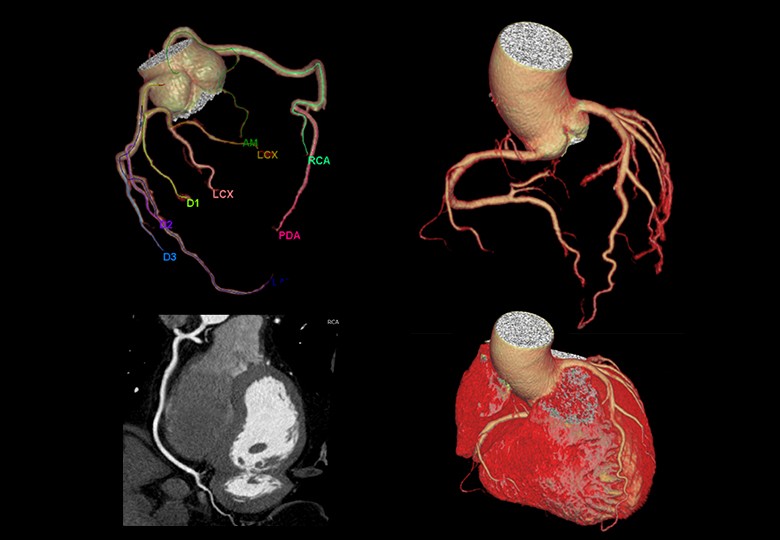

Coronary Scan